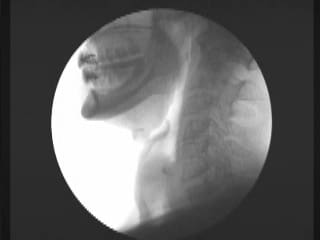

lateral image